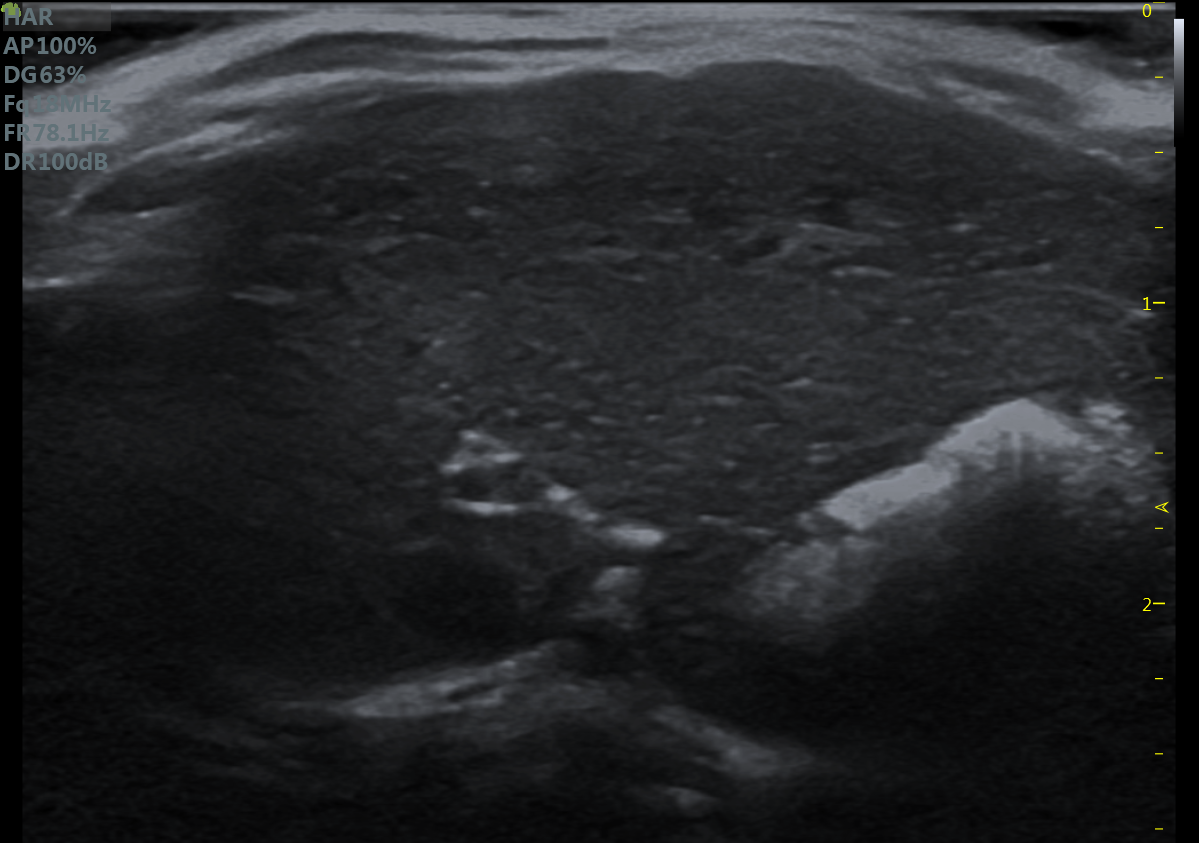

23MHz高频探头,优秀卓越的浅表显影

RF Flow充盈不外溢 Xcen超高频浅表显影